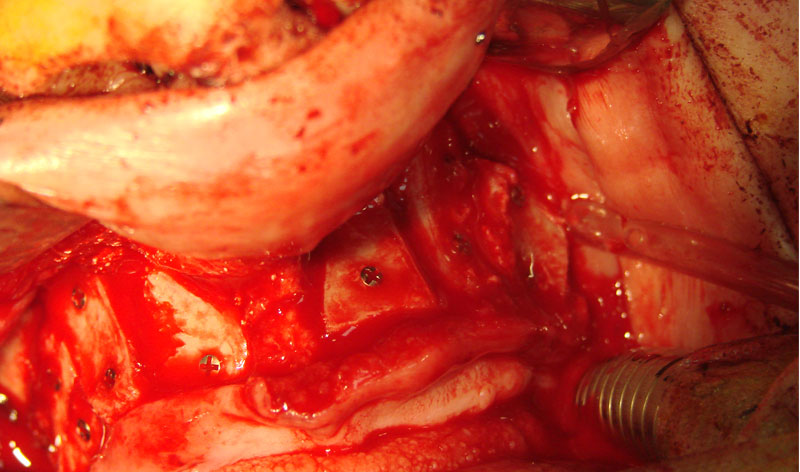

Existen muchas situaciones donde la pérdida y la atrofia ósea son tan graves que nos obligan a recurrir a la cresta iliaca del paciente, para conseguir el volumen óseo necesario para la correcta reconstrucción del maxilar. Así, la colocación de implantes será posible a los 3 meses.